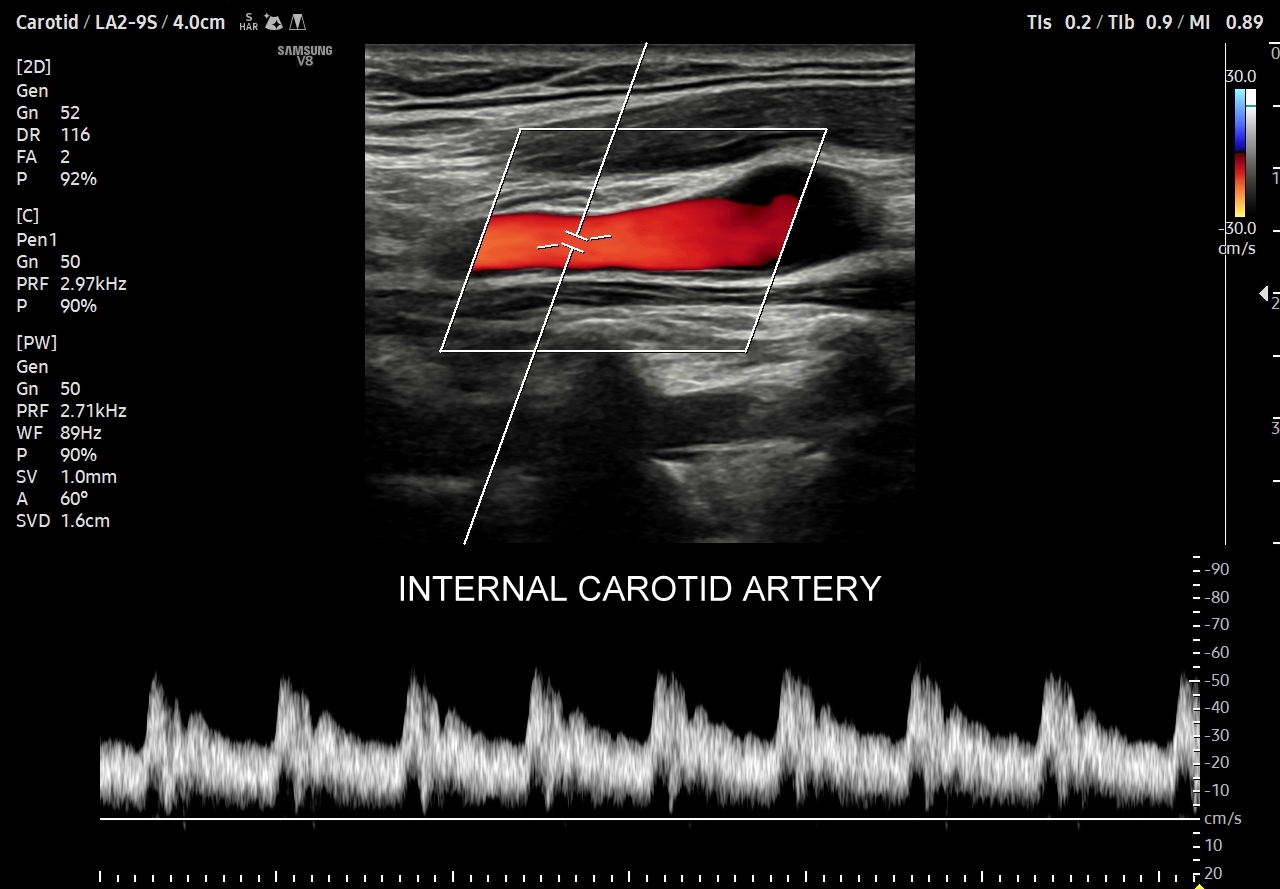

- Profile o niskiej pulsacyjności (ang. low-pulsatility) cechują się szerokim pikiem skurczowym, praktycznie ciągłym przepływem przez całą fazę rozkurczową i monofazowością. Profile tego typu występują w tętnicach unaczyniających bezpośrednio mózg, siatkówkę, tarczycę, wątrobę, śledzionę, nerki.

Podsumowując, przepływ krwi w konkretnych tętnicach, w tym jego przyspieszenie i prędkość, wynikają z 1/ charakteru pracy pompy, tj. serca; 2/ stanu naczyń per se, tj. elastyczności i drożności; oraz z 3/ właściwości biologicznych unaczynionego narządu. W związku z powyższym prawidłowy profil przepływu we wszystkich rodzajach tętnic w krążeniu dużym w warunkach fizjologicznych, tj. przy zdrowym sercu, zdrowych naczyniach i zdrowym docelowym narządzie, zawsze cechuje się szybkim narastaniem prędkości przepływu, czyli stromym ramieniem wstępującym; krótkim czasem akceleracji (ang. acceleration time) od początku tegoż ramienia do pierwszego załamania na nim, tj. zasadniczo nie przekracza 70 ms, a zwykle oscyluje wokół 30 ms. Poza tym w przypadku młodych i elastycznych tętnic podążających do kończyn, tj. naczyń z przepływem wysokooporowym, w fazie rozkurczowej przepływu obserwuje się wyższe załamki i często więcej załamków (zamiast jednego nawet do trzech). W krążeniu płucnym czas akceleracji prawidłowo przekracza 100 ms.

Kolejnym i bardzo ważnym wskaźnikiem określającym przepływ w naczyniu tętniczym jest wspomniany już opór przepływu. Jego kwantyfikacja w postaci określenia wskaźnika oporu RI wykorzystywana jest praktycznie przy badaniu funkcji miąższowych narządów wewnętrznych w organizmie (np. nerki, wątroby, mózgu), a także w ramach oceny biologii tkanek nowotworowych, czy zapalnych w celu przeprowadzenia tzw. oceny multiparametrycznej MPUS. Otóż w przypadku narządów, głównie miąższowych, o stałym lub/i wysokim metabolizmie przepływ tętniczy poza szczytem skurczowym utrzymuje się stale w okienku rozkurczowym. Im mniejsza różnica pomiędzy szczytową prędkością skurczową (PSV, peak systolic velocity) a prędkością końcowo-rozkurczową (EDV, end diastolic velocity) tym niższy jest opór i wskaźnik oporu, który to wylicza się z następującego wzoru: RI = (PSV-EDV) / PSV.